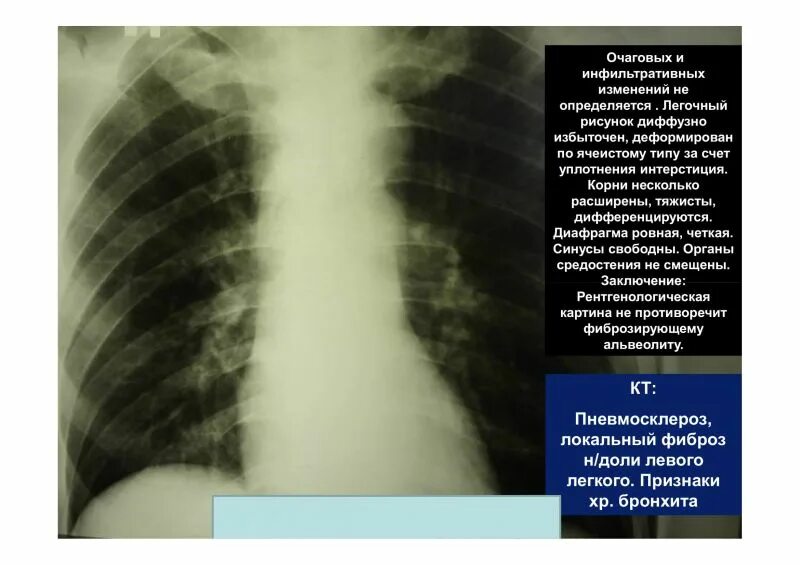

Легочной рисунок диффузно деформирован